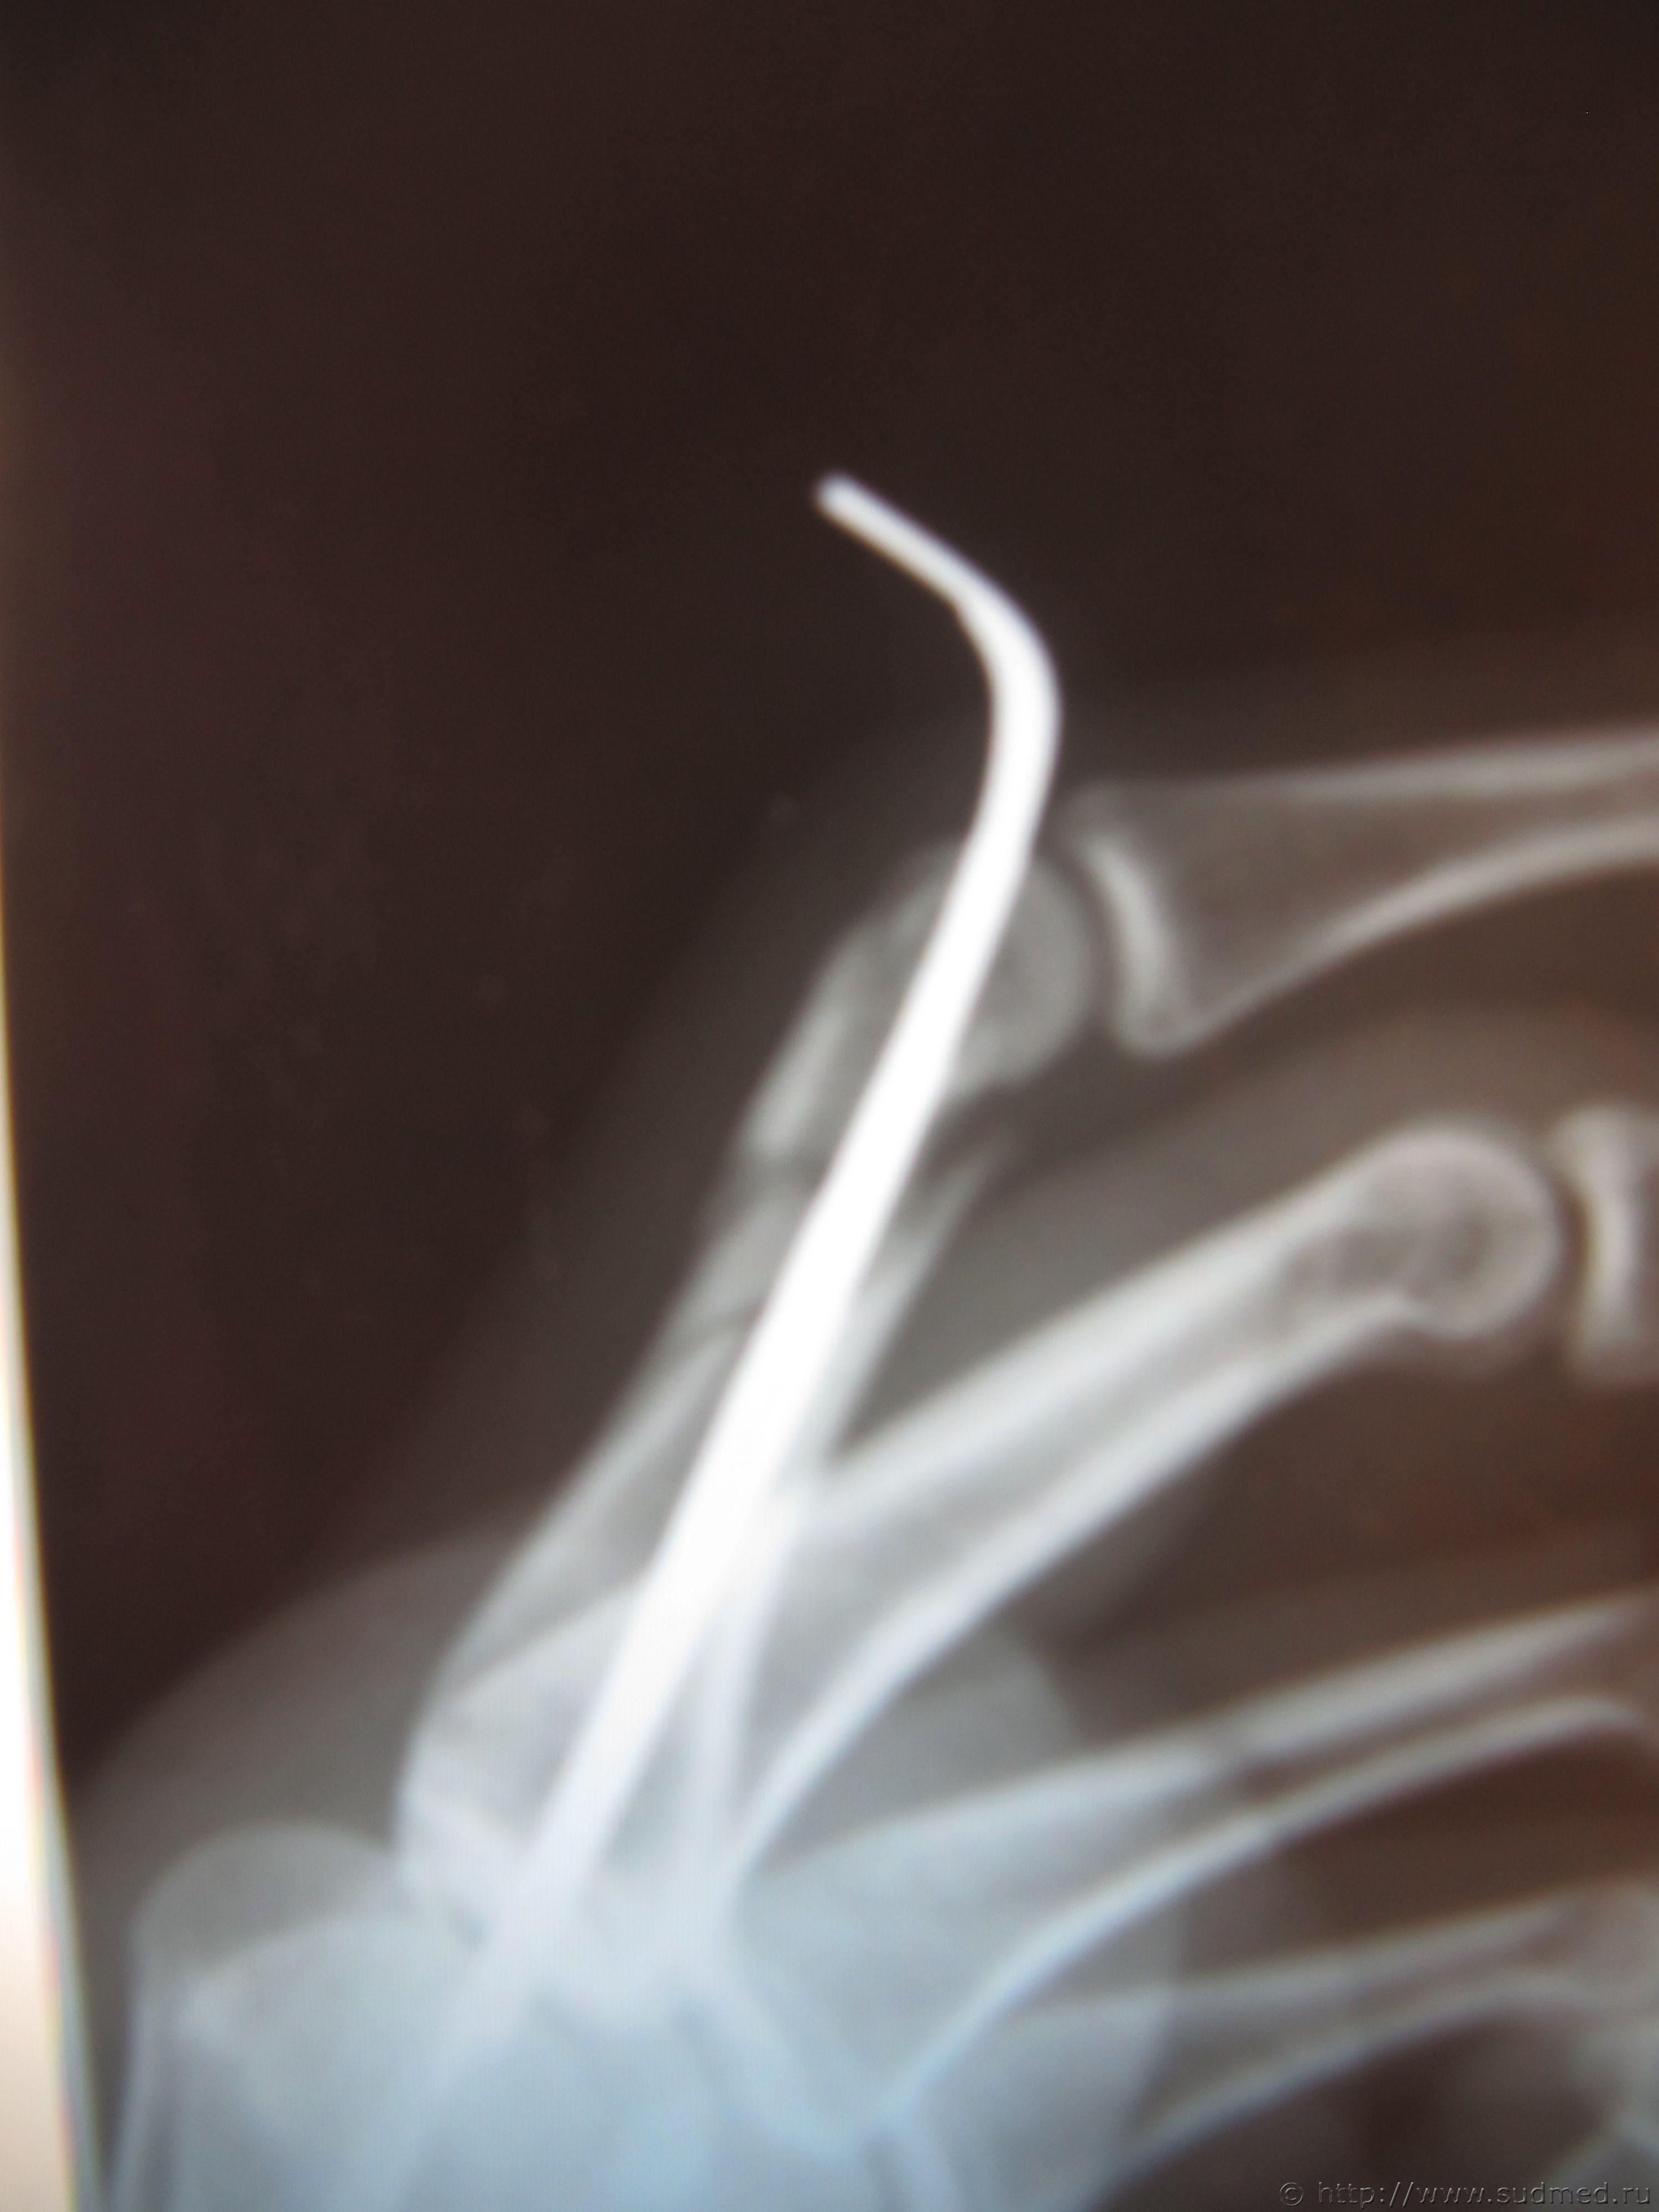

По описанию нашего рентгенолога: перелом нижней трети основной фаланги 2-го пальца правой кисти внутрисуставной оскольчатый Т-образный,к отосланным рентгенограммам, прошу коллег высказать мнение насчет механизма перелома и оценки двух версий

1. выкрутили пальцы

2. удар кулаком по лицу

Но на первом снимке - перелом кости основной фаланги 2 пальца, а на втором - перелом второй пястной кости.

В любом случае - перелом дистальной трети основной фаланги не может образоваться в следствии ротации пальца, не может образоваться вследствии удара кистью сложенной в "кулак".

Может образоваться при непосредственном ударе в эту область каки-то предметом.

Деформация сжатия вдоль оси кости.

В прямой проекции - перелом классически Т-образный, в боковой - создает впечатление косого. В сумме получается жизнеспособной только версия про "удар кулаком по лицу" (либо не сомкнутым кулаком, если удар был "прямым"/не буду подробно расписывать общепонятный боксерский термин/, либо сомкнутым, но удар был "открытой перчаткой", т.к. действие травмирующей силы практически совпадало с продольной осью основной фаланги). При выкручивании никак не получится перелом, видимый на прямой проекции. Исключается.

Абсолютно согласен - осевая нагрузка (и только так образуются "Т"-образные переломы эпифизов, но тут еще и зона сжатия на тыльной поверхности, разрыва - на ладонной, а значит нагружение было по оси и с отгибанием дистальной части в сторону тыла. Механизм вероятнее всего осевое воздействие при приведенной средней фаланге, близко к прямому углу относительно оси основной фаланги (возможно, конечно и при падении, но вообще типично для удара сложенными в "каротистском" варианте пальцами кисти, - удар сгруппировано согнутыми межфаланговыми суставами (между основными и средними), при выпрямленных и параллельных плюстнам основных фаланг)

Перелом, судя по его локалзации и морфологии образовался в результате вертикального нагружения на кость основной фаланги второго пальца.

Это могло быть как при полностью выпряменном пальце (с нагружением на ногтевую фалангу), так и при непосредственном вертикальном нагружении фалаланги при согнутом в первом межфаланговом сустеве пальце - при

Такой механизм нагружения присутствует при ударе выпрямленном или согнутым пальцем о твердую поверхность и полностью исключен при вращательном (ротационном) нагружении при выворачивании пальца.